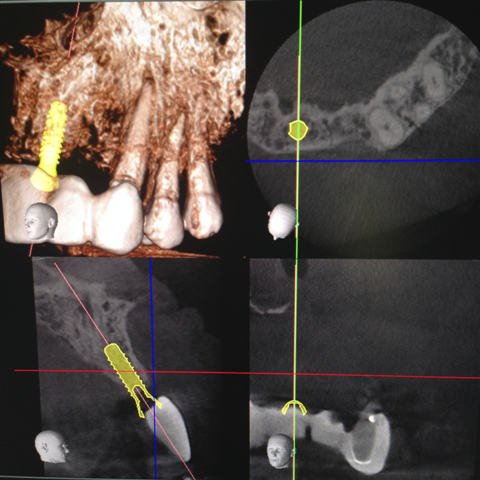

A 3-D x-ray unit is also an essential and dynamic part of our daily clinical service. Of the most remarkable developments in modern radiology, the 3-D unit is a workhorse in characterizing micro-pathology (like tooth lesions, cysts, and sometimes cracks, etc) as well as mapping out the topography of planned implant sites (including the sinuses), root canal spaces and internal configurations, as well as TMJ (jaw joint) anatomy. The technology is high in working value for routine clinical dentistry (root canals, surgery, diagnostic, follow-up) and has advanced considerably in the past decade. While once more of a research tool, it is smart tech utilized in our office in some way every single day. We use a limited field of view (FOV) to allow the dentists to dynamically review the case, often just after completing a clinical examination. A small FOV scanner is advantageous and different than wide FOV that other offices may employ if not for different reasons.